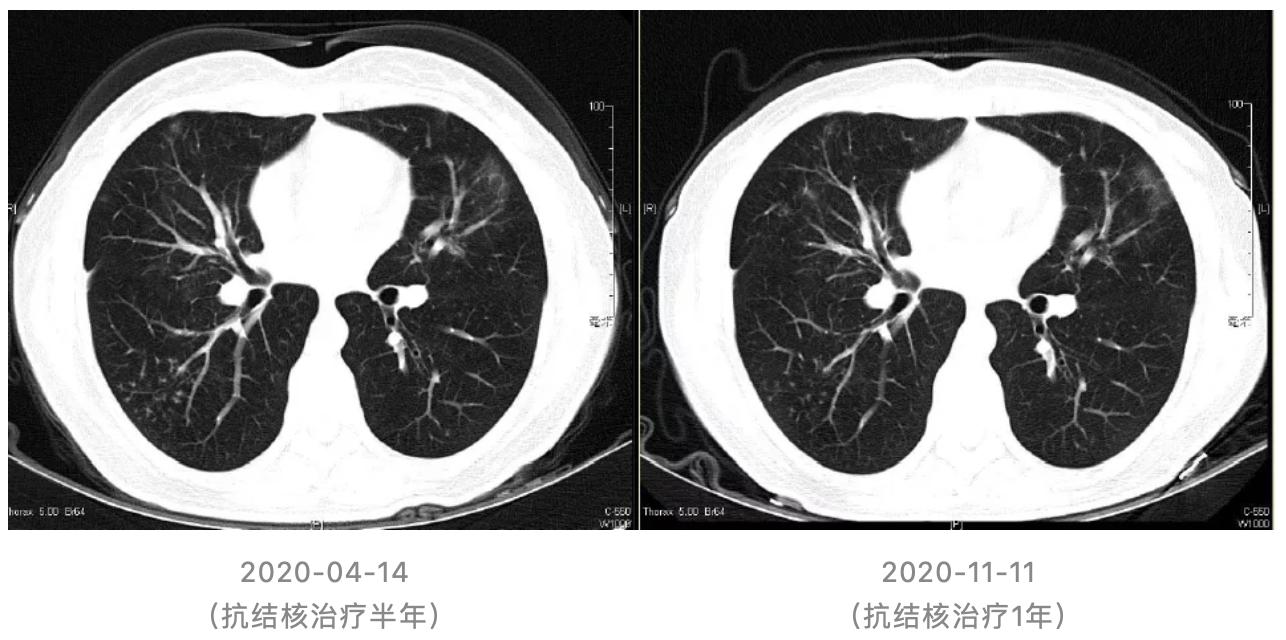

(1)抗结核治疗1月后随访胸部CT:

(2)抗结核治疗1年随访胸部CT: